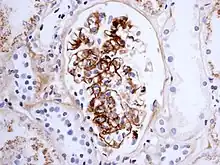

As observed under methods of histopathology, acute necrotizing vasculitis within the affected tissues is observed concomitant to neutrophilic infiltration, along with notable eosinophilic deposition (fibrinoid necrosis). Often, immunofluorescence microscopy can be used to visualize the immune complexes.[7] Skin response to a hypersensitivity of this type is referred to as an Arthus reaction, and is characterized by local erythema and some induration. Platelet aggregation, especially in microvasculature, can cause localized clot formation, leading to blotchy hemorrhages. This typifies the response to injection of foreign antigen sufficient to lead to the condition of serum sickness.[6]